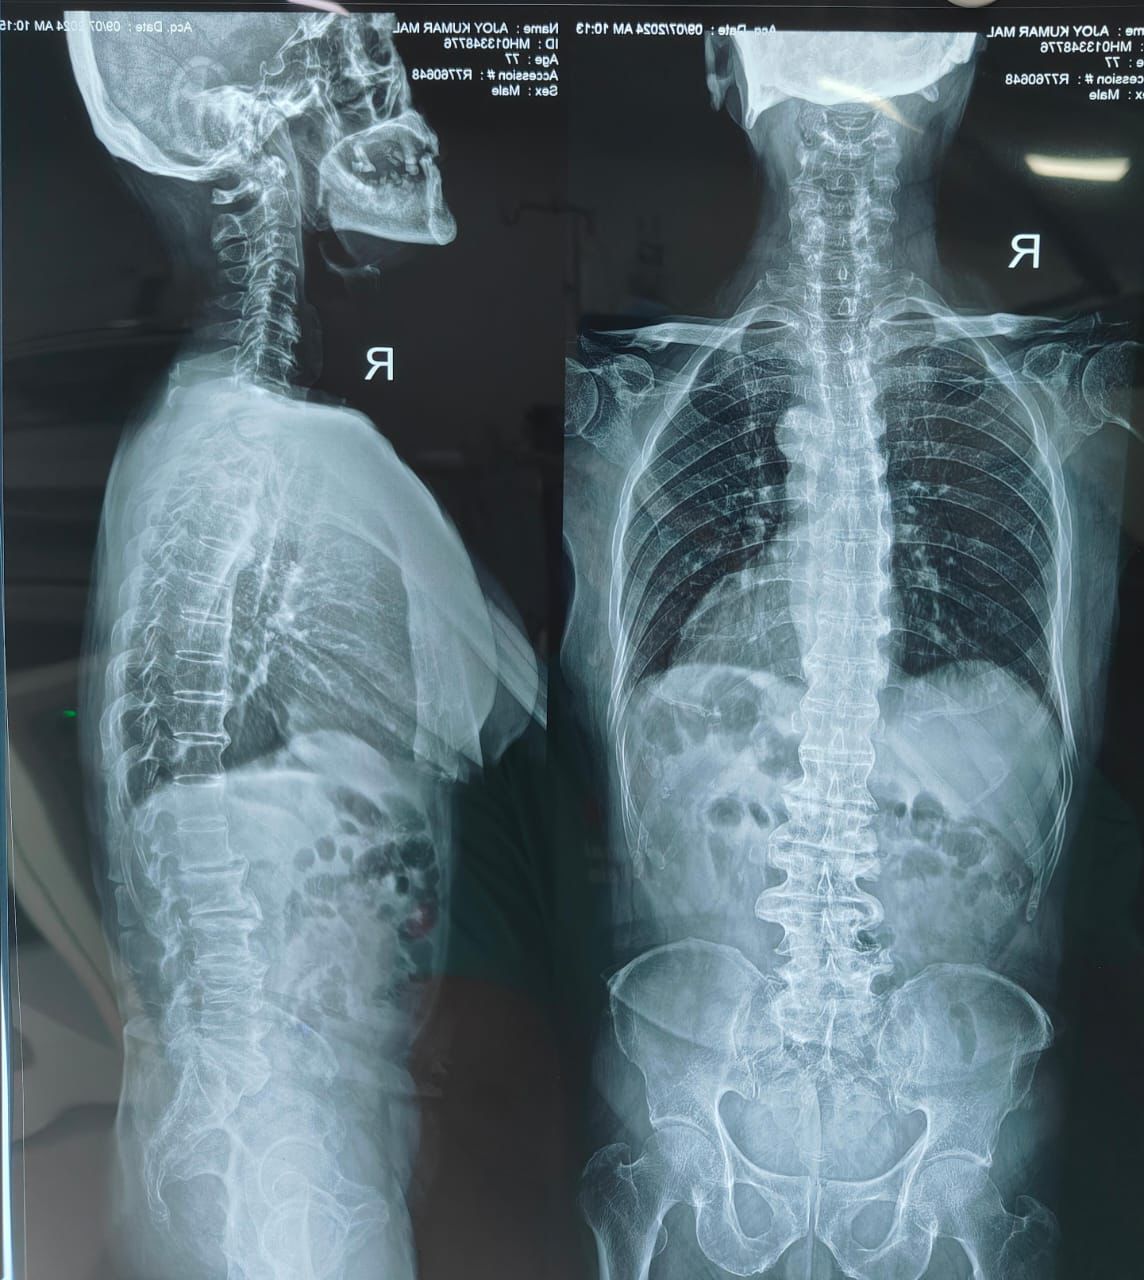

হাসপাতালে বিস্তারিত মূল্যায়নের পর অজয়বাবুর ক্ষেত্রে ধরা পড়ে জটিল একটি স্পাইন সমস্যা— ডিজেনারেটিভ ল্যাম্বার স্কোলিওসিস, অর্থাৎ মেরুদণ্ডের পাশে বেঁকে যাওয়া এবং সেই সঙ্গে ছিল ‘ক্যানাল স্টেনোসিস’। অর্থাৎ মেরুদণ্ডের মধ্যবর্তী স্নায়ু পথ সংকীর্ণ হয়ে যাওয়া। এই জটিল সমস্যাগুলির কারণে তাঁর স্নায়ুতে চাপ পড়ছিল এবং সেটাই ব্যথা ও চলাফেরার সমস্যার মূল কারণ হয়ে দাঁড়িয়েছিল।

অস্ত্রোপচারের আগে।